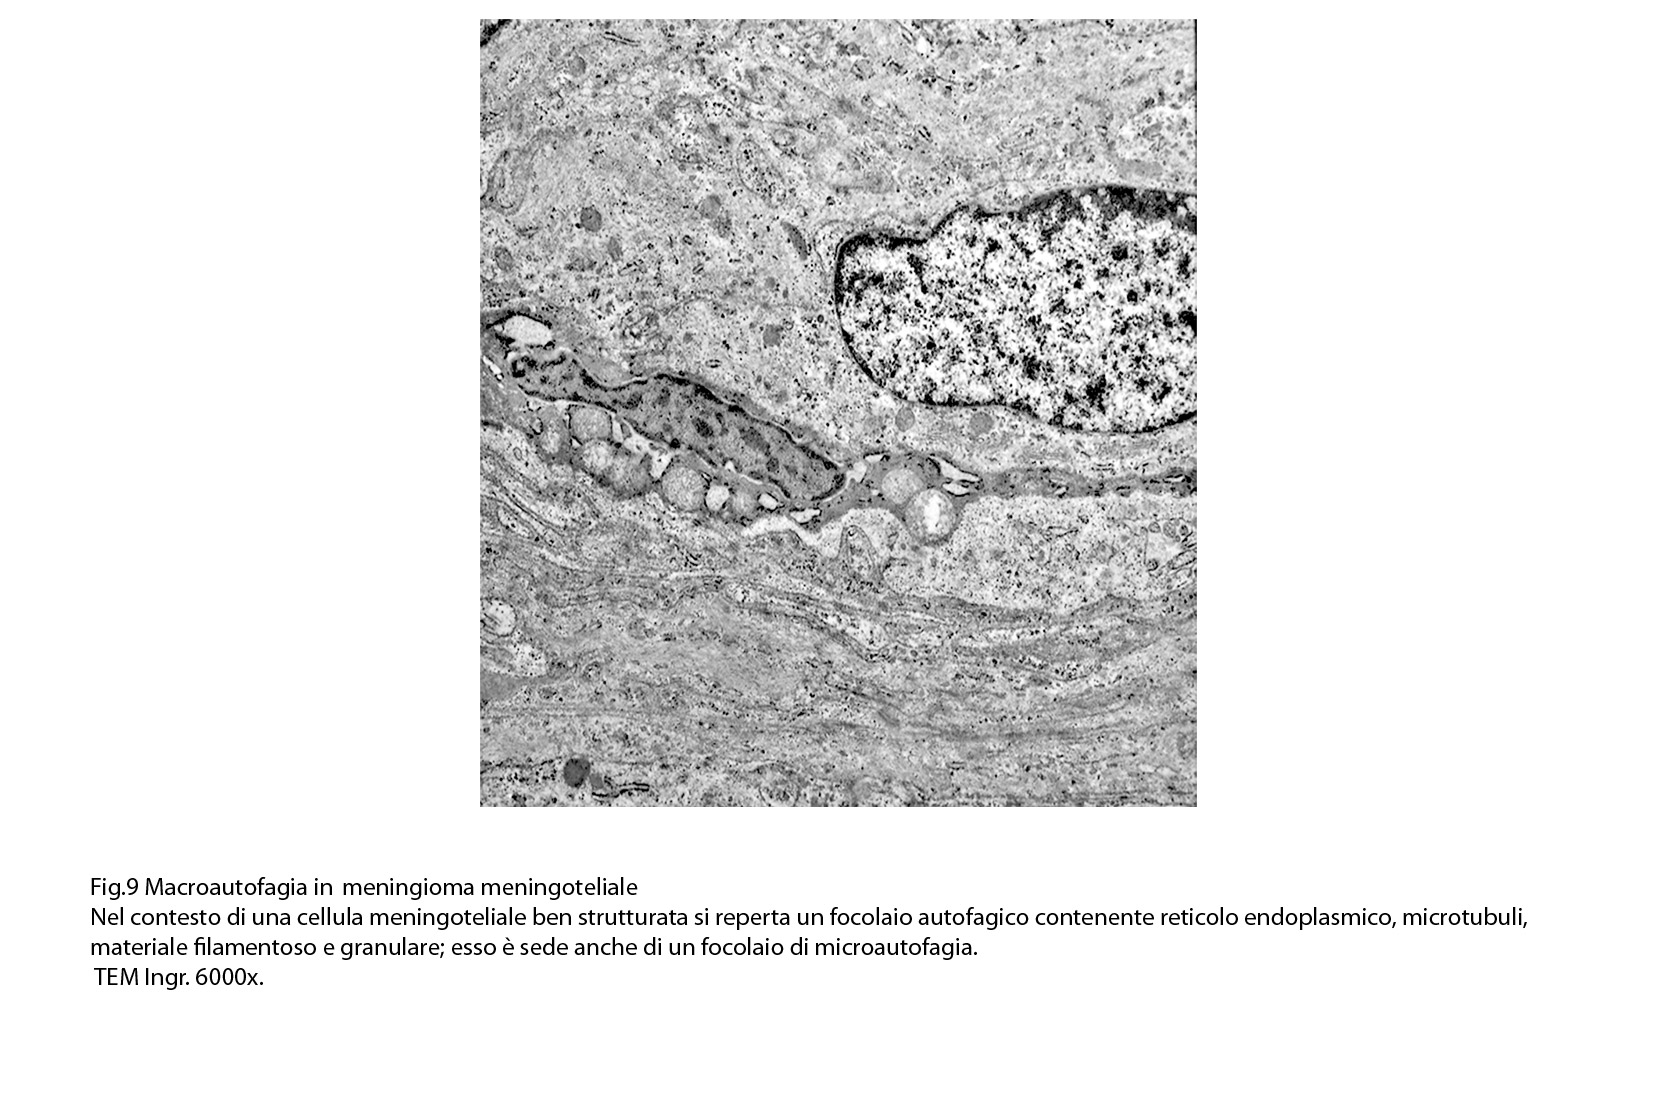

Sono repertabili anche cellule meningoteliali ben strutturate e ricche di organuli marcate da un focolaio di autofagia contenente frammenti di substrutture e materiale filamentoso.

Anche a livello di prolungamenti citoplasmatici di cellule meningoteliali si riscontra la presenza di due focolai autofagici occupati in parte da materiale amorfo.